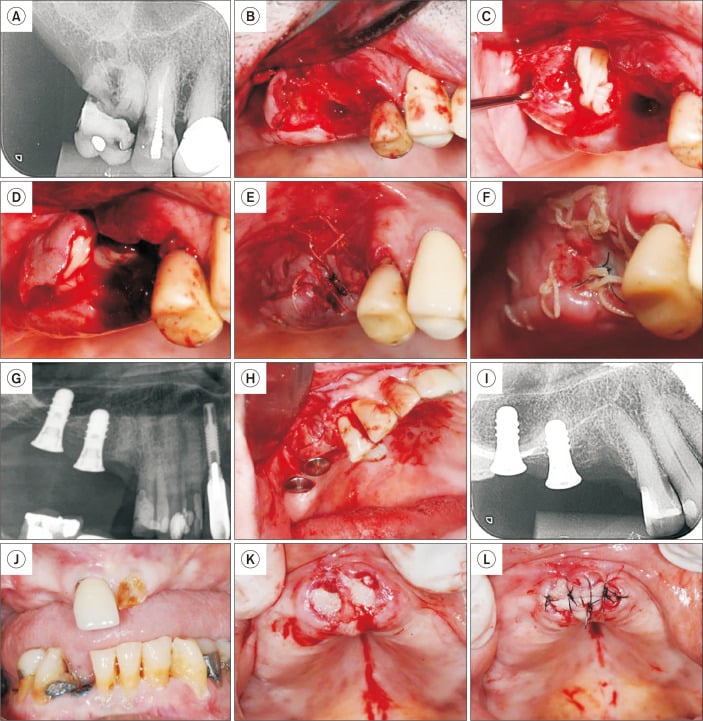

Bone socket preservation with leukocyte platelet-rich fibrin (L-PRF).

Bone socket preservation with leukocyte platelet-rich fibrin (L-PRF). A. Initial periapical radiograph of Patient 3, showing extensive coronal destruction of tooth 16. B. Following extraction, a sizable purulent collection was observed in the distal root area, which was curetted. C. An L-PRF plug and membrane were placed in the area that was curetted. D. An L-PRF plug and membrane were also placed in the mesial root area. E. Immediate suture. F. Clinical appearance 15 days post-extraction. G. Initial radiograph of Patient 4, showing a root remnant in the region of tooth 15, adjacent to implants. H. After root extraction, L-PRF membranes were positioned both in the alveolar area and around the neighboring implant. I. Immediate periapical radiograph post-extraction. J. Patient 5, with a history of cancer treatment, presenting teeth 11 and 21 indicated for extraction. K. L-PRF plugs positioned in each socket. L. L-PRF membrane sutured over the sockets. Note that exposure of the L-PRF membrane in the oral cavity does not pose any issues.